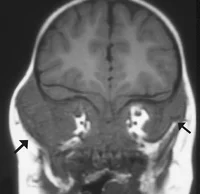

Rhabdomyosarcoma = Embryonal Sarcoma

- Most common primary solid orbital malignancy of childhood

- Average age at presentation 7-8 years

- Sudden onset and rapid evolution of unilateral proptosis

- 90% 5 years survival rate with timely and appropriate treatment